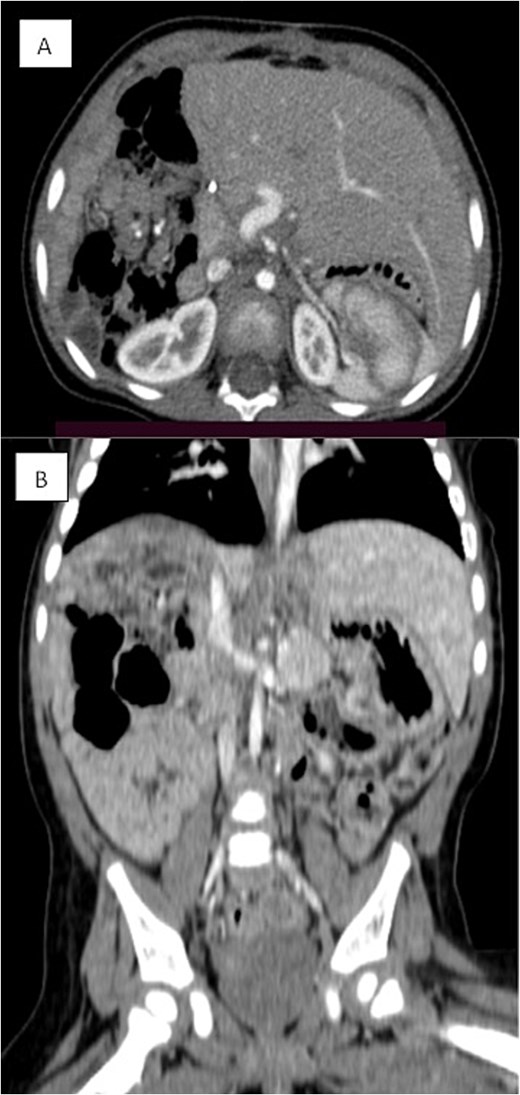

A right-sided hepatectomy was initially planned; however, intraoperatively, the tumor was resected with a safe margin while preserving unaffected liver tissue. Postoperative liver volumetry confirmed adequate remaining liver volume (40%) (Fig. 3). Surgery was completed without complications.

Triphasic CT examination of the abdomen post-right hepatectomy. (A) The axial view shows a clear operative bed with no residual enhancing lesions or collections. The (B) coronal view demonstrates compensatory hypertrophy and enlargement of the left hepatic lobe. Herniated bowel loops are visible, filling the right hypochondrial subphrenic region.